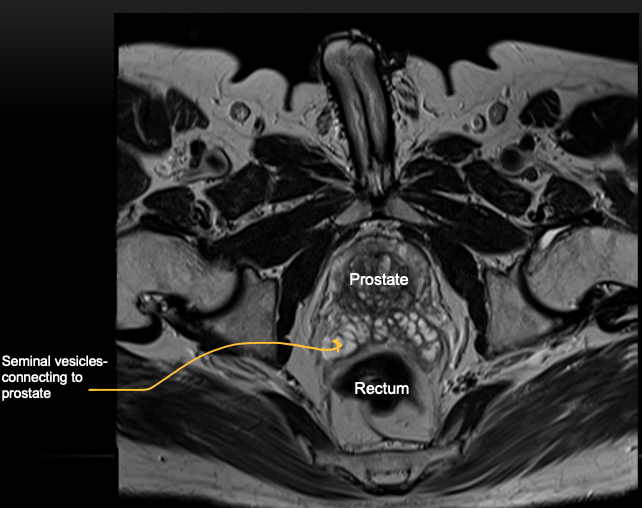

Q

What type of imaging modality is this & fill in the blanks

A

MRI prostate, axial